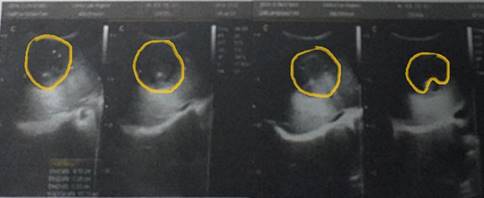

At the children's emergency room, an abdominal bloating was assessed by means the abdominal examination with a 3 cm palpable hepatomegaly below the right costal margin. The assessment of the ultrasound study of the abdomen, referred from the ambulatory and shown in Figure 1, revealed a liver enlarged in the right anterosuperior area of the right lobe at hepatic segment VIII.

From the ultrasound study analysis, a rounded space-occupying lesion, predominantly solid, with mixed-echo patterns, a volume of 65.5 cc and it not vascularized on Doppler, was also assessed. As a conclusion of the ultrasound study, the following is presented: findings in probable relation with liver abscess, without intrahepatic dilatation of bile ducts. However, the quality of the ultrasound images is very poor.